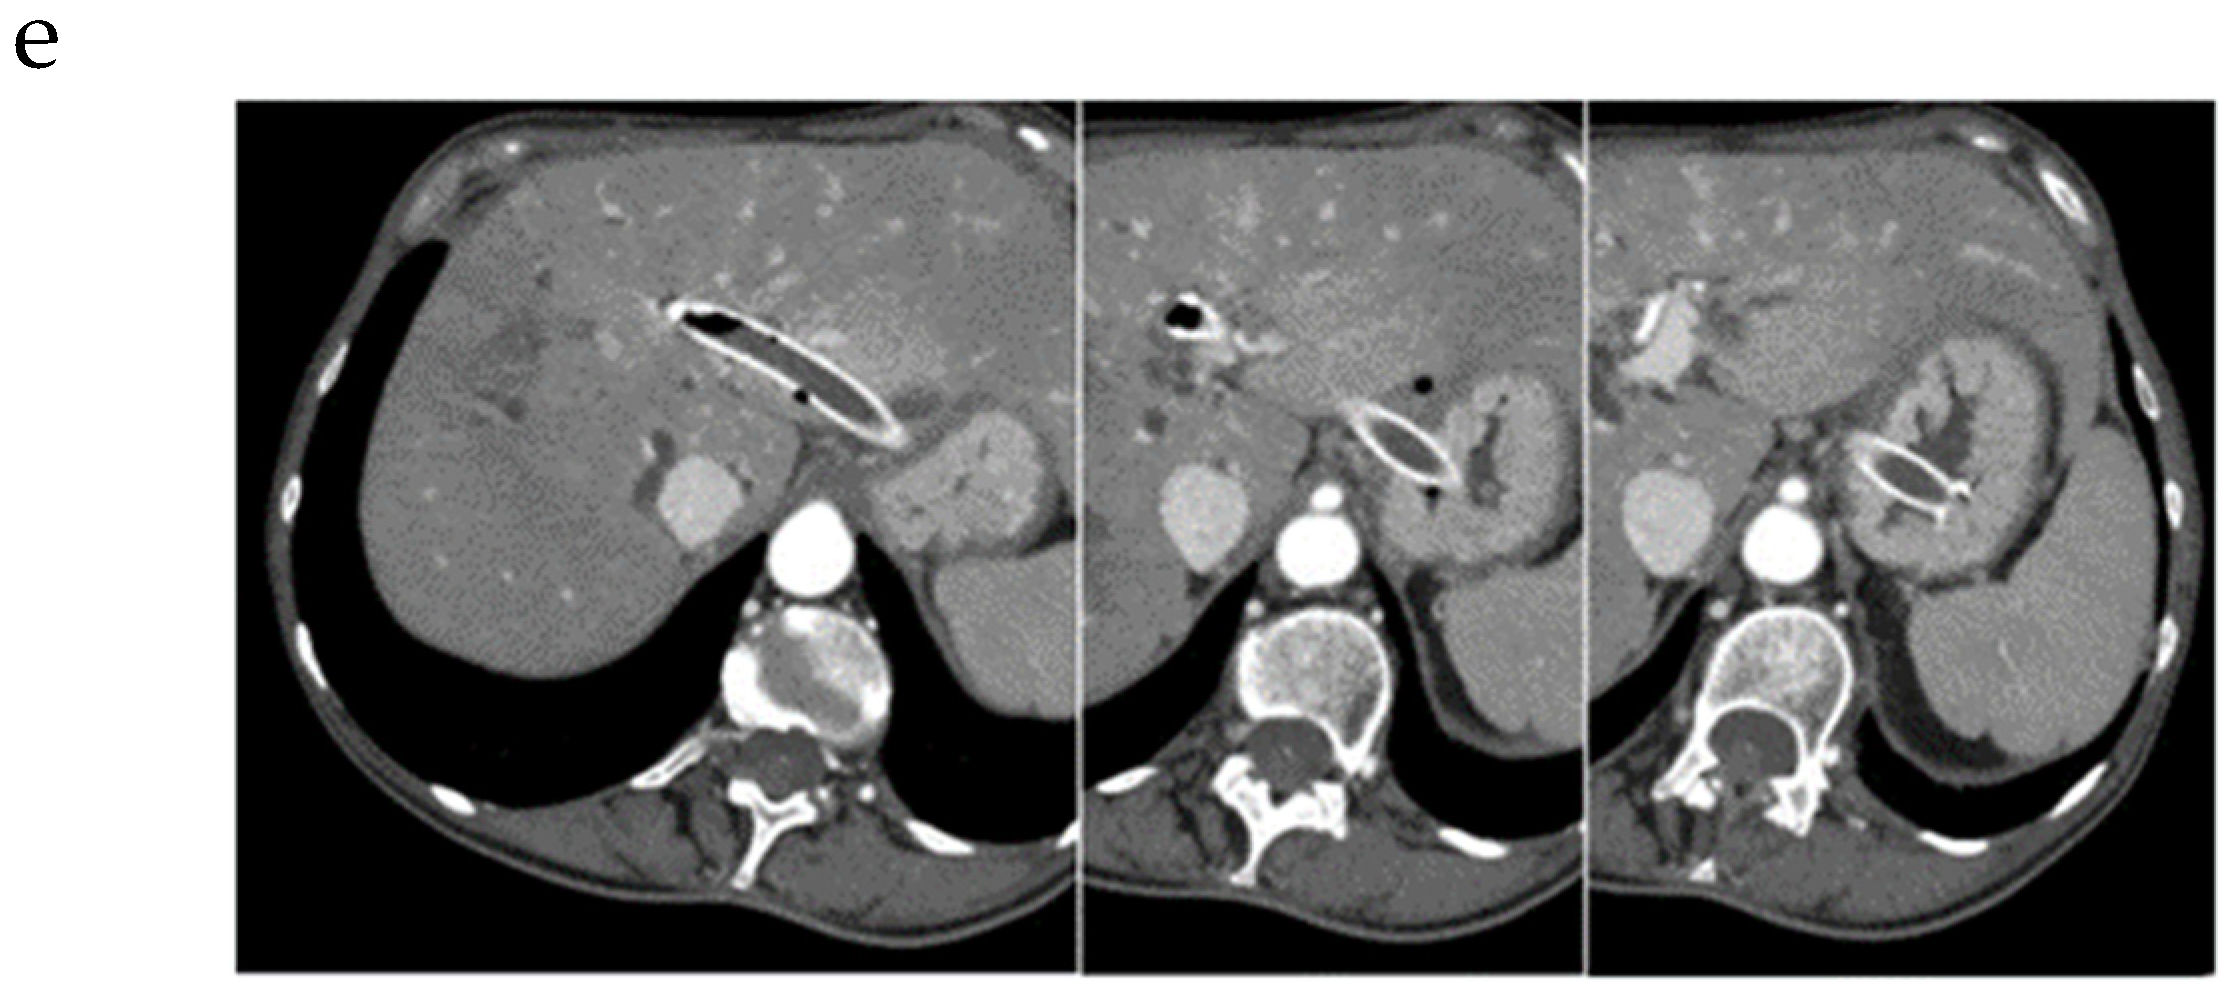

5. Rendezvous Techniques

5.1. Should Rendezvous Be Used First?

5.2. Which Rendezvous Route Should Be Used?